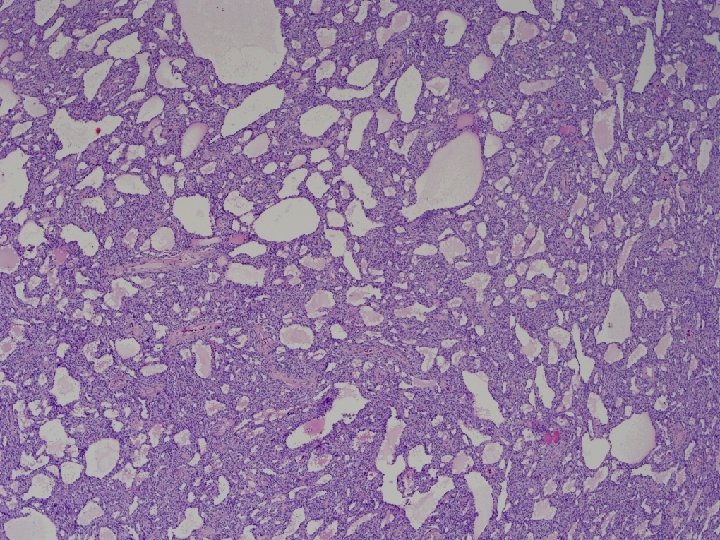

48 y. o. woman Adnexal mass, 14 cm

Macroscopy • 14 x 11 x 10 cm mass • Encapsulated, bosselated, multinodular with solid cut surface

• Mixtures of growth patterns with solid and cystic components: Granulosa, adult-type?

• Mixtures of growth patterns with solid and cystic components: Granulosa, adult-type? - too much cytoplasm - no Call-Exner - no nuclear grooves

• Non-grooved nuclei and some foci looking somehow follicular: Granulosa, juvenile-type?

Granulosa, juvenile-type ? • 48 yo • No thickened layer of granulosa cells lining the « follicular spaces » Robboy’s 2009 • Chromatine is fine and evenly distributed (vs coarse chromatine, hyperchromatic nuclei in juvenile granulosa) • No mitoses (vs brisk in juvenile granulosa) • No luteinisation (frequent in juvenile granulosa)

Microscopy • Growth patterns: - Cystic or sieve-like (with eosinophilic secretions) - Tubular - Solid (sheets of cells or closely packed tubules) • Cells: - Epithelioid to fusiform - Pale to eosinophilic cytoplasm • Nuclei: - Round to oval with uniform chromatin - No or few mitotic figures